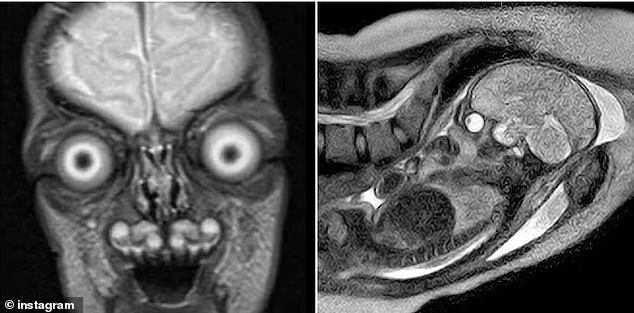

Disturbing images of fetal MRIs have resurfaced online, sparking renewed debate about the safety and necessity of magnetic resonance imaging during pregnancy. The scans, which reveal the intricate skeleton of a developing baby in stark contrast to surrounding tissue, have left many viewers unsettled. The stark whiteness of bones against dark soft tissue, combined with the eerie appearance of fluid-filled eyes, has led some to describe the images as 'fossils preserved inside the living body.'

Public reactions to the viral images have ranged from fascination to fear. Social media comment sections are filled with visceral responses: 'Terrifying or hilarious, depending on your mood,' one user wrote. Others questioned the humanity of the scans, with one declaring, 'That's definitely not a human baby.' Such reactions highlight the psychological toll these images can take, even as they underscore the medical value of MRIs in diagnosing life-threatening fetal conditions.